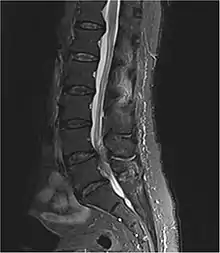

| Diagnostic method | Medical imaging (MRI, CT scan)[1][3] |

The cause is usually a disc herniation in the lower region of the back.[1] Other causes include spinal stenosis, cancer, trauma, epidural abscess, and epidural hematoma.[1][2] The diagnosis is suspected based on symptoms and confirmed by medical imaging such as MRI or CT scan.[1][3]

Diagnosis is first suspected clinically based on history and physical exam and usually confirmed by an MRI scan or CT scan, depending on availability.[4] Bladder scanning and loss of catheter sensation can also be used to evaluate bladder dysfunction in suspected cases of cauda equina syndrome and can aid diagnosis before MRI scanning. Early surgery in acute onset of severe cases has been reported to be important.[4]